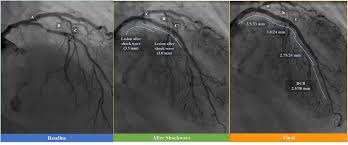

Intravascular Lithotripsy For Treatment Of Severely Calcified Coronary Artery Disease Journal Of The American College Of Cardiology X Mol

Intravascular Lithotripsy In Calcified Coronary Lesions Circulation Cardiovascular Interventions

Intravascular Lithotripsy May Offer Solution For Calcified Coronary Lesions Daic

Intravascular Lithotripsy For Treatment Of Severely Calcified Coronary Artery Disease The Disrupt Cad Iii Study Tctmd Com

The primary effectiveness endpoint of procedural success was 924. Multivessel disease is often associated with a higher burden of comorbidities. The primary effectiveness endpoint of procedural success was 924. People with coronary artery disease will have calcification of the blood vessels. There was no ECG gating. Primary outcome segmented by median age was the first occurrence of mechanical noninvasive or invasive ventilation extracorporeal membrane oxygenation ECMO or death within 30 days of. Mean calcified segment length was 479 188 mm calcium angle was 2925 765 and calcium thickness was 096 025 mm at the site of maximum calcification.